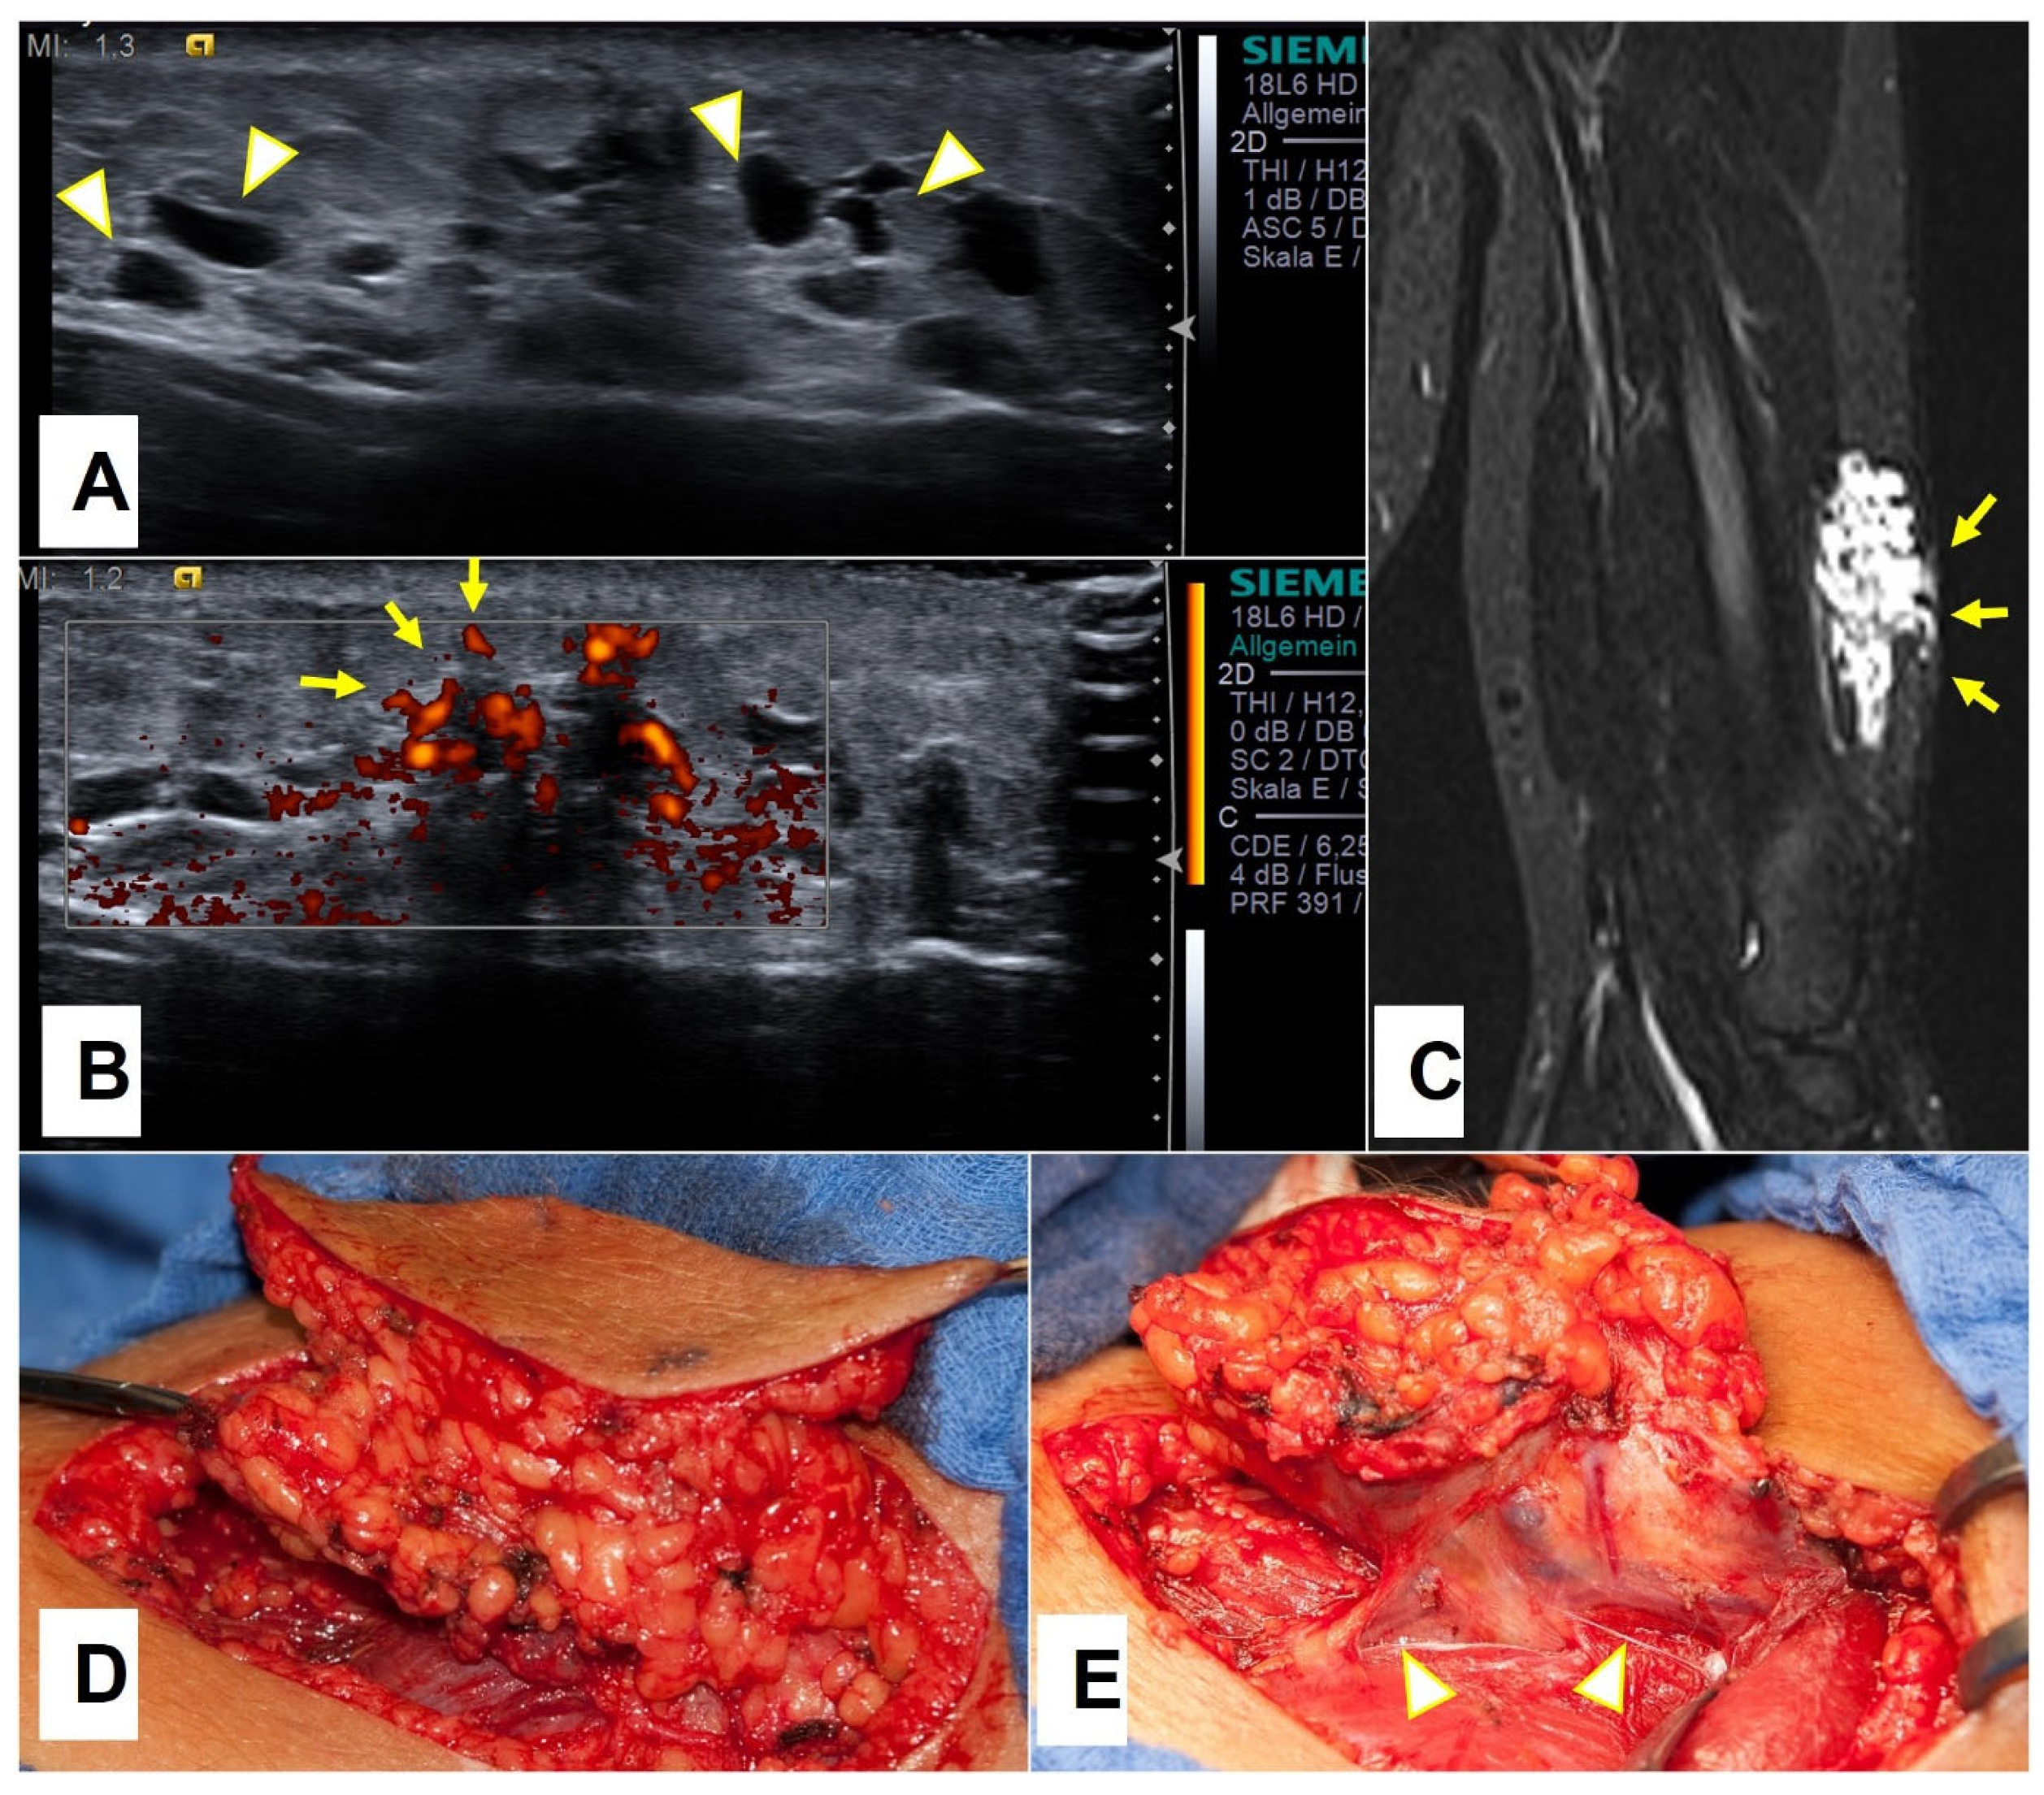

Seventeen patients (36%) presented after their 10th year of life, and nine (53%) of these patients presented after a sudden enlargement of their lesions. Altogether, 18/47 patients (38%) with only subcutaneous extension of their low-flow vascular malformations presented after a sudden enlargement of their SVM due to intracystic bleeding, most of which occurred in patients older than three years. The most common location for the SVM was the upper extremity; in particular, the axillary and upper arm region (Figure 6), where more than half of the SVM of our cohort were located, as shown in Table 2.

Figure 6.

A 14.5-year-old boy was presented because of the minor swelling on his left upper arm, which appeared after he started to go to the gym. Ultrasound imaging showed a tubulo-cystic lesion (arrowheads) on the lateral aspect of his upper arm (A) which showed perfusion (arrows) in a power Doppler mode with venous flow characteristics (B). MRI depicted a venous malformation (arrows) of the localized extension located in the subcutaneous area (C). Complete excision of the VM was performed (D). Draining veins are depicted with arrowheads (E).

3.2.2. Presentation on Ultrasound

At their initial encounter, each SVM patient underwent an ultrasound examination. The SVMs were mainly described as ill-defined masses of heterogeneous echotexture with visible multiple cystic spaces within. In cases that presented with sudden enlargement and recent or past bleeding into the cysts, a clear-cut sedimentation line was noted through the cyst representing the clot retraction as a pathognomonic sign of intracystic bleeding (see Figure 5). In five patients with SVM, no clear cystic areas were described during the ultrasound examination.